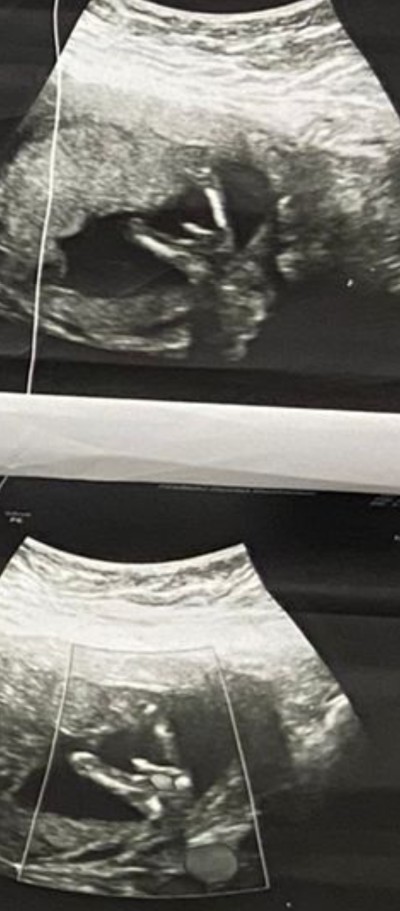

Benim 14 hafta erkek dedi dun degisirmi bnde mrk edoyorum resim atsam anlarmisin acaba bacak arasi bu gordonmu acaba

image

(518 puan)

Kocaman pipisi var annesi kesin erkek hayırlı olsun

Yaa kordonda olma ihtimali vardir belki dr net demedi kagida yazdi verdi gorumceme ben aksam ogrendim o yuzden bana aciklama yapmadi diger kontrolumu beklicem artik

Kesinlikle erkek gibi geldi bana canım iki erkek cocugumda böyleydi ama tabi en son doktorun dedigi önemli